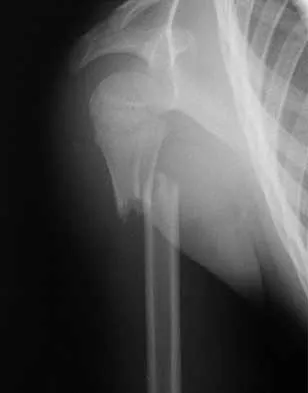

Which of the following findings is seen in the chest radiograph shown in Figure 13?

Orthopaedic surgeons are often responsible for interpreting radiographs of general examinations such as the chest radiograph shown. For accurate interpretation, it is important to systematically review all of the information available on the radiograph. Using this approach, the fracture of the left proximal humerus is readily recognized. Linear air soft-tissue density at the lung periphery would suggest a pneumothorax, but this finding is not shown on the radiograph. The upper thoracic spine is well aligned. The sternoclavicular and distal clavicles are normal.